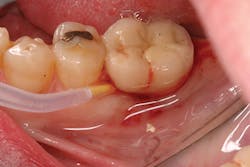

Treatment of peri-implant mucositis can often be accomplished via nonsurgical mechanical therapy. Although systemic antibiotics have been shown to reduce inflammation associated with peri-implant gingival tissue, as a monotherapy, they have been shown to be ineffective due to the bacterial recolonization of the implant surface without mechanical debridement.(12) Studies show that proper scaling and root planing with attention to bacterial plaque removal can be effective in reducing peri-implant mucositis lesions.(13) Localized drug delivery has also shown to have a positive effect in reducing mucositis lesions in conjunction with mechanical debridement (Fig. 2), especially in the areas of the mouth that are hard to reach.(14) After nonsurgical intervention, the patient should be recalled within three weeks. If no resolution of the inflammation has occurred, surgical intervention should occur.(15)